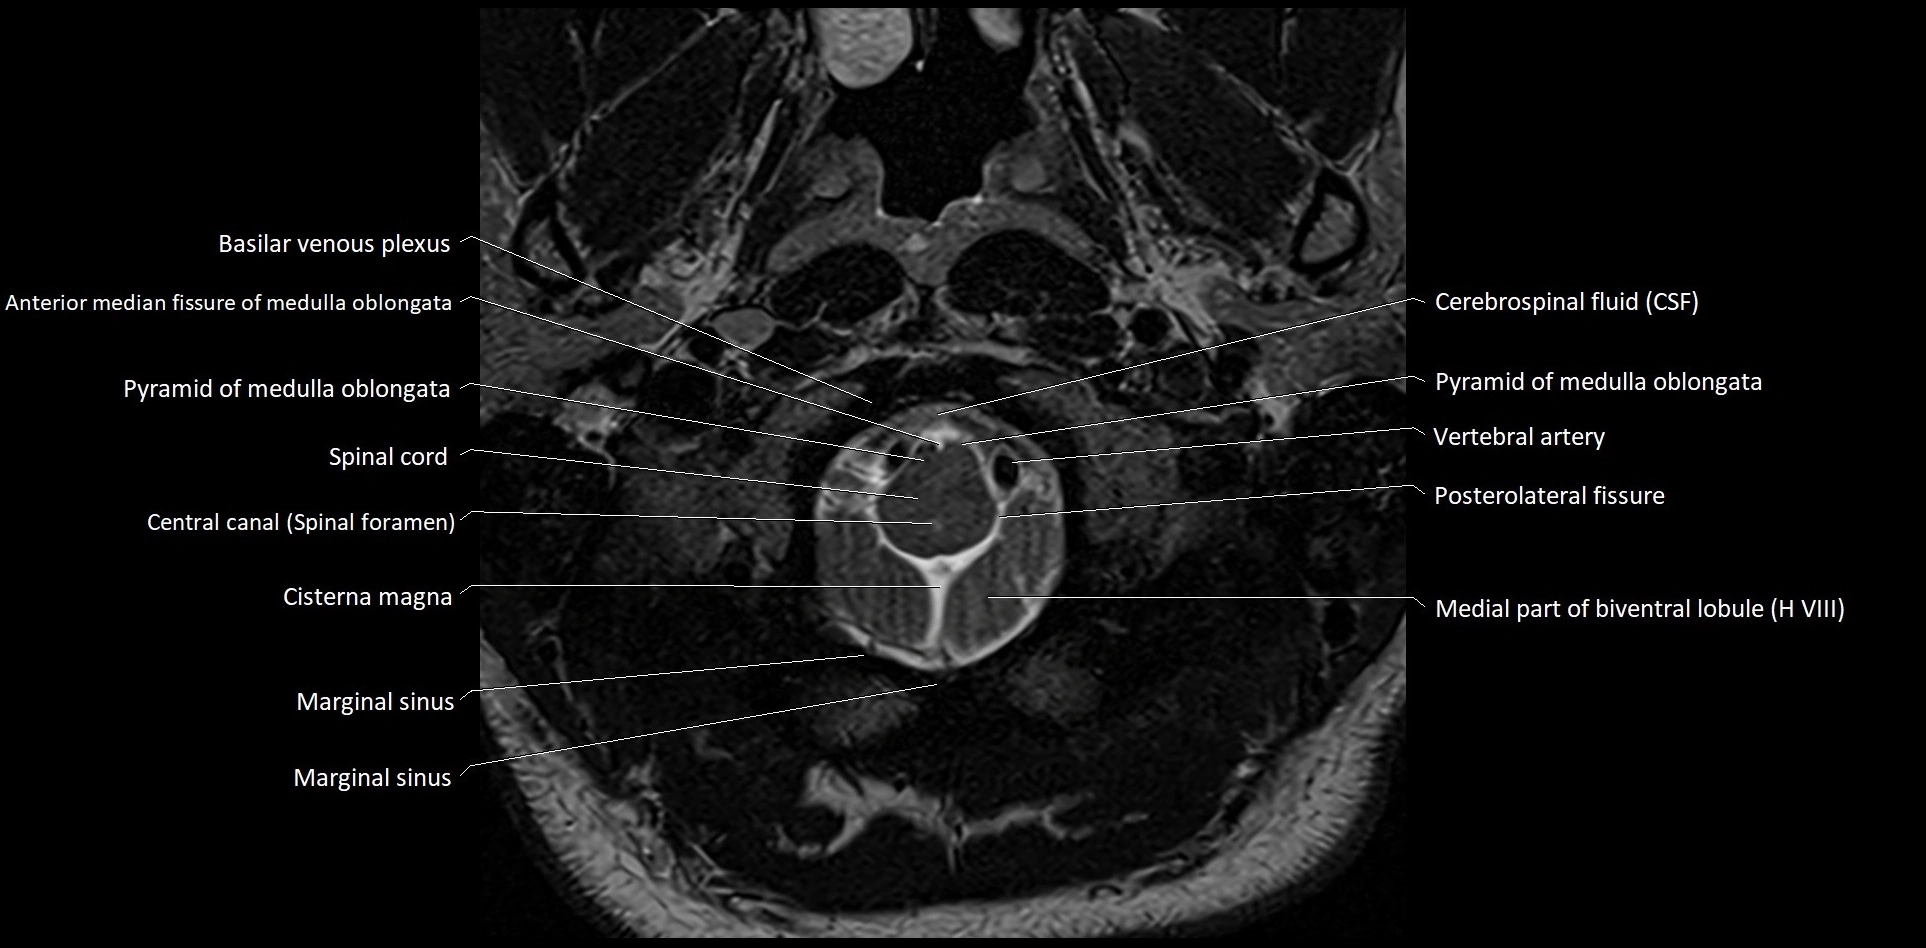

MRI images